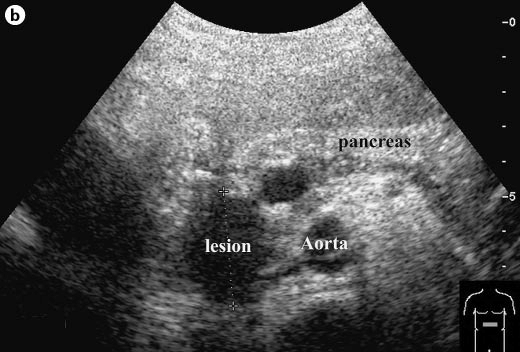

Akut hasnyálmirigy gyulladás (acut pancreatitis)

Ezeken a képeken több hasnyálmirigy gyulladást láthatunk. A felső (a) képen csillaggal van jelölve a hasnyálmirigy, ami kiszélesedett, echoszegény. Körülötte a nyilak oedemás zsírra mutatnak, ami szintén a gyulladás következménye.

A másik két képen is (b és c) szintén kissé echoszegényebb és kiszélesedettebb hasnyálmirigyet láthatunk amelyek körül folyadék jelent meg, ugyancsak a gyulladás következménye képpen..